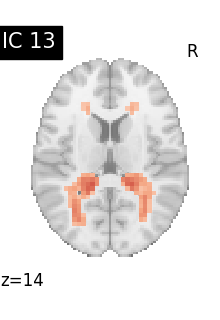

Finally, we plot the map for each ICA component separately

from nilearn.image import iter_img

from nilearn.plotting import plot_stat_map, show

for i, cur_img in enumerate(iter_img(canica_components_img)):

plot_stat_map(

cur_img,

display_mode="z",

title=f"IC {int(i)}",

cut_coords=1,

vmax=0.05,

vmin=-0.05,

colorbar=False,

)

show()